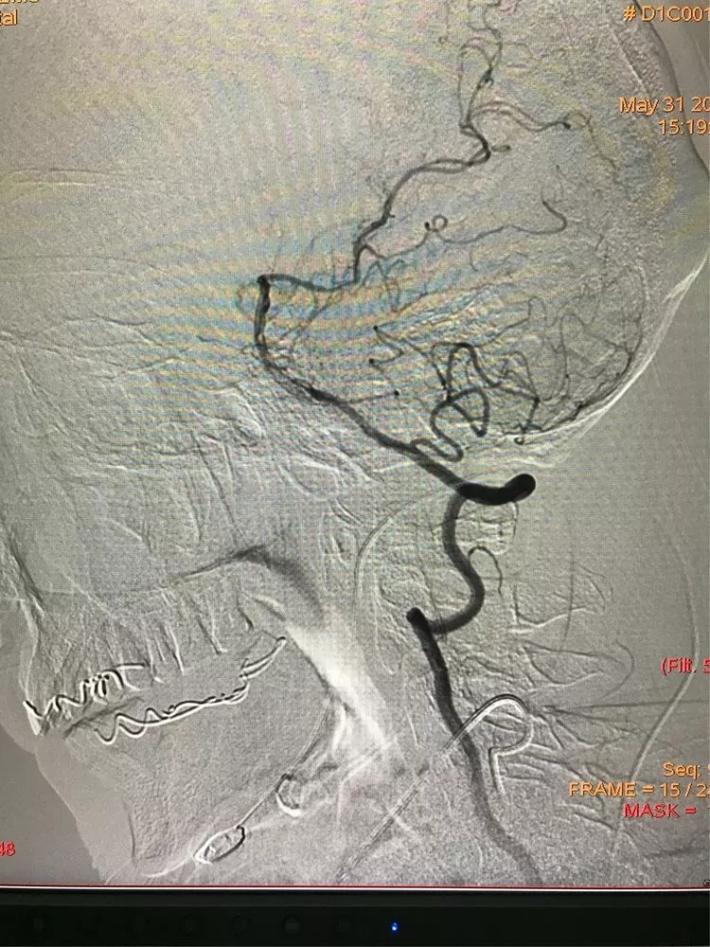

MRA检查显示:基底动脉闭塞。

手术步骤

桥接动脉取栓,造影显示:基底动脉闭塞。

微导管进入基底动脉尖部,显示进入真腔。

置入支架,见基底动脉有血流。

取出支架,血管闭塞。

第二次上微导管进入真腔。

置入支架,基底动脉有血流。

取出支架,血管未开通。

第三次上微导管。

支架打开取栓。

见基底动脉血流恢复,左侧大脑后动脉血流欠佳。